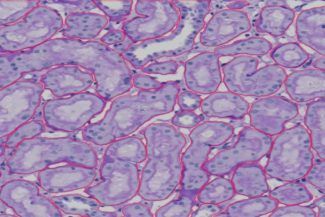

This image appears to be a histological section stained and viewed under a microscope, likely showing tissue structures with cellular and extracellular components. The red lines outline specific areas, probably marking regions of interest, which could be different tissue compartments or specific cellular formations. The quality of the image is clear, with distinct staining allowing for the differentiation of various cell types and structures. The quantity of marked areas suggests a detailed analysis, possibly for diagnostic or research purposes, highlighting numerous regions within the sample. The overall resolution is sufficient to observe cellular details, making it valuable for precise histopathological evaluation.

This picture shows a second dyed and microscope-observed histological slice, most likely at a different magnification or area. The tissue’s different features are indicated by the red outlines. These structures resemble tubules or glandular forms, presumably from a kidney or similar glandular organ. Due to efficient staining, the picture quality is excellent and allows for simple identification of nuclei and other cellular elements. There is also a clear distinction between cellular and extracellular components. The number of indicated structures suggests a careful method of emphasizing particular regions of interest, implying a thorough examination for research or diagnostic reasons. The tissue architecture can be seen in great detail thanks to the exceptional resolution, which makes it an invaluable tool for histopathological analysis.

this image shows tubulus and PTC and how they connected

this image it show the all structures that we annotated